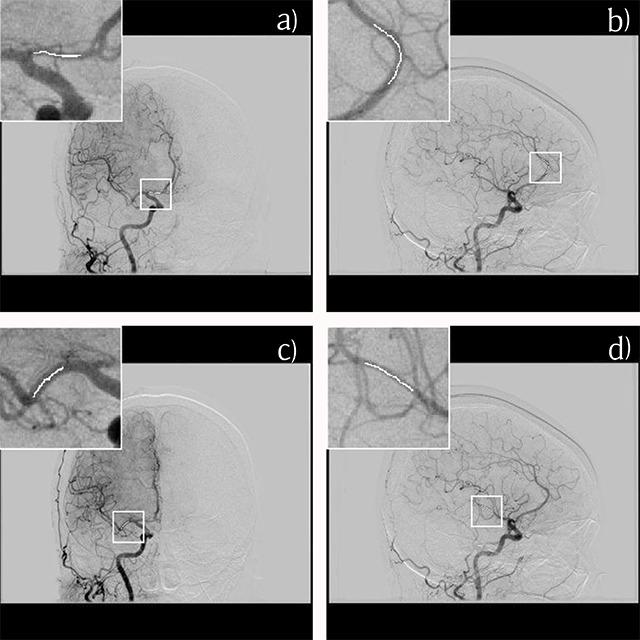

Twenty-four patients who underwent 3D DSA of the common carotid artery from June 2013 to March 2015 were included in this retrospective study. Contrast enhancement of each patient was analyzed for four cerebral arteries segments (A1, A2, M1 and M2) by measuring the average pixel value on the source rotational two-dimensional DSA images. Linear regression analysis was used to investigate the correlation between injection rate and contrast enhancement.

All four regression lines showed that a higher injection rate led to higher contrast enhancement. There was a significant relationship for the A1, A2 and M1 segments (P = 0.008, 0.03 and < 0.001) but not for the M2 segment (P = 0.13). The goodness-of-fit of the regression lines was high for the M1 segment (R = 0.63). However, as the size of the vascular lumen became narrower, the value for the A1 (R = 0.28) and A2 (R = 0.19) segments became lower.